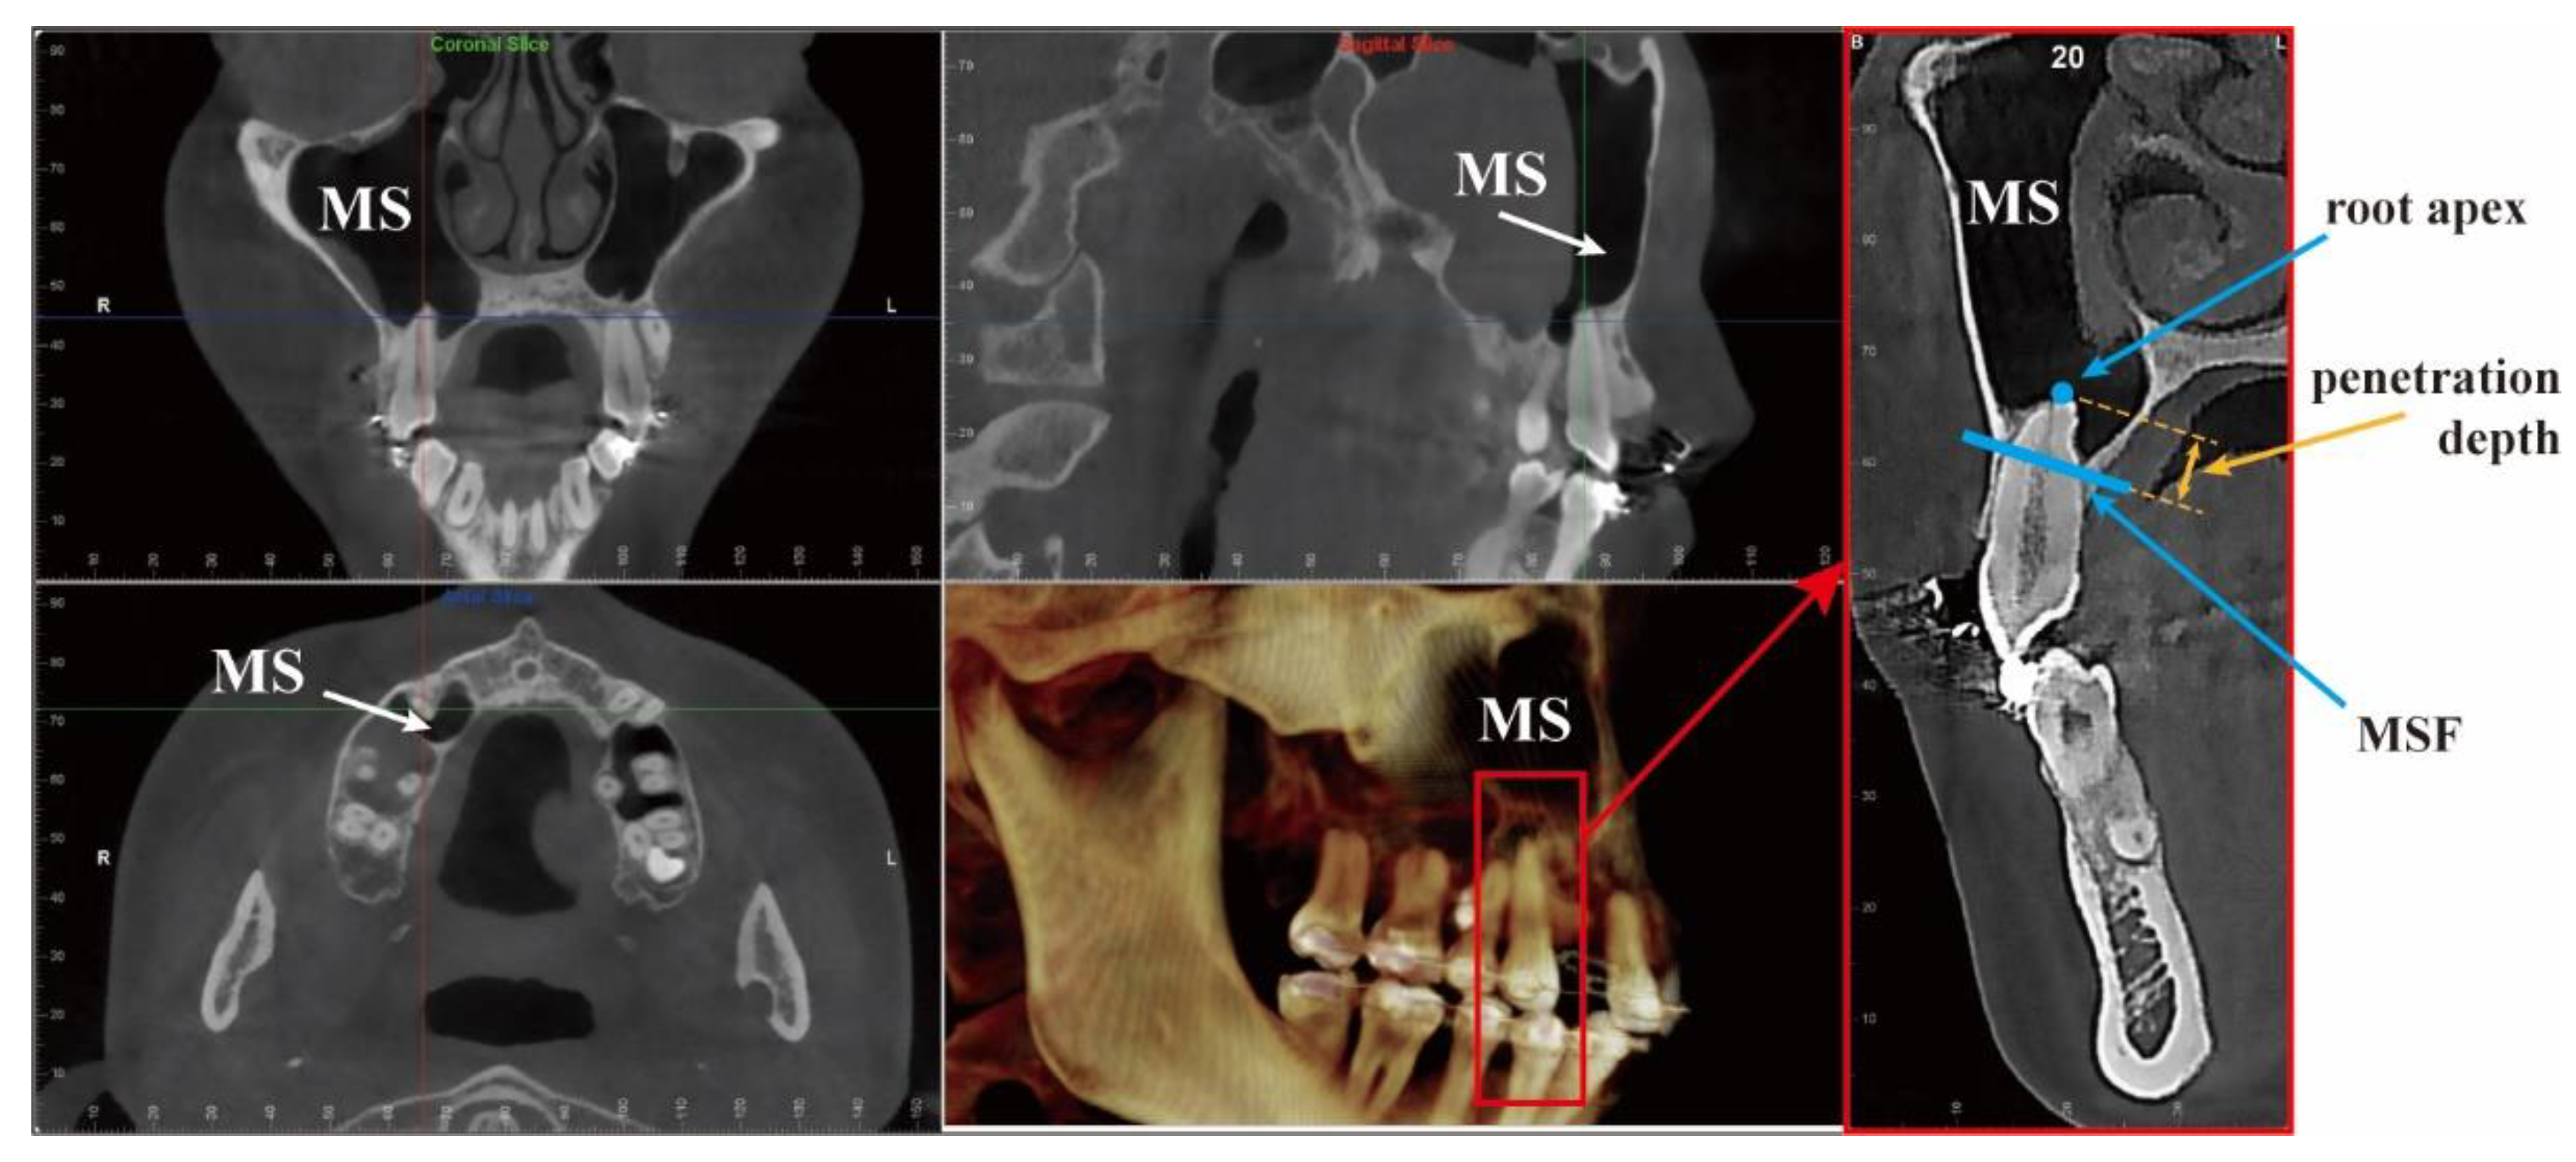

3D models were constructed from tomography images. We used the cone-beam computed tomography (CBCT) image of a patient with low MSF (Figure 1) from the Affiliation 2. The tomography was scanned using a NewTom 5G (version FP, Imola, Bologna, Italia) under the following settings: mode (81.5 mGy·cm, 110 KVP, and 5 mA); voxel size, 0.25 mm; and slice thickness, 0.25 mm. The scan was originally taken for diagnosis before orthodontic treatment.

Figure 1.

Tomography images of a patient with a low MSF. Penetration depth is the distance between the root apex and the MSF; MS is the maxillary sinus; MSF is the maxillary sinus floor.